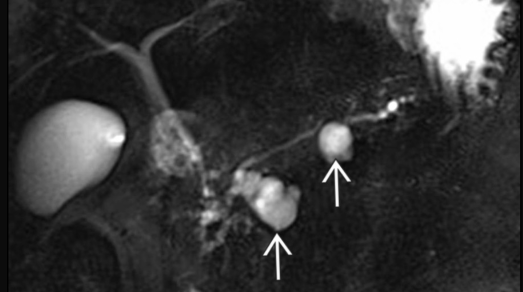

- Communication avec Wirsung = clé

Wirsung dilaté et tortueux avec gonflement de l’ampoule, atrophie du pancreas